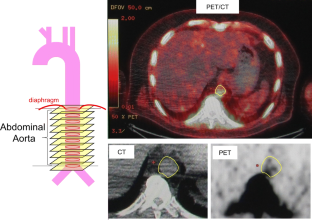

Prostate cancer patients who had at least 3 NaF PET-CT scans over at least 1.5 years were retrospectively enrolled. Regions of interest were traced in the abdominal aorta on both PET and CT images, excluding skeletal NaF activity. The maximum standardized uptake value (SUVmax) of NaF and the density and volume of calcium (exceeding 130 HU) were summed and divided by the number of slices to produce the SUVmax/slice and the mm3·slice−1 of calcium.

Figure 1